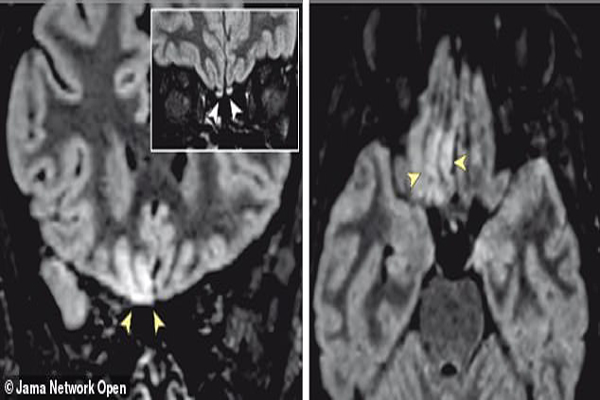

اخیرا اسکن های متعدد از مغز یک فرد مبتلا به کرونا نتایج جالب توجهی را نشان داده است. این فرد یک دختر 25 ساله ایتالیایی است که در مرکز رادیوگرافی واقع در رم زندگی می کند. او در روزهای نخست ابتدا فقط سرفه می کرد اما به تدریج حس بویایی خود را هم از دست داد. MRI از مغز این فرد نشان داد قسمت هایی که در مغز مربوط به حس بویایی می شوند بیشتر سفید شده اند.

این سفید شدن در پی به علت حملات التهابی ویروس کرونا به وجود آمده است.

در تصویر زیر قسمت های بویایی که در پی التهاب کرونایی سفید شده اند در عکس مشخص است: